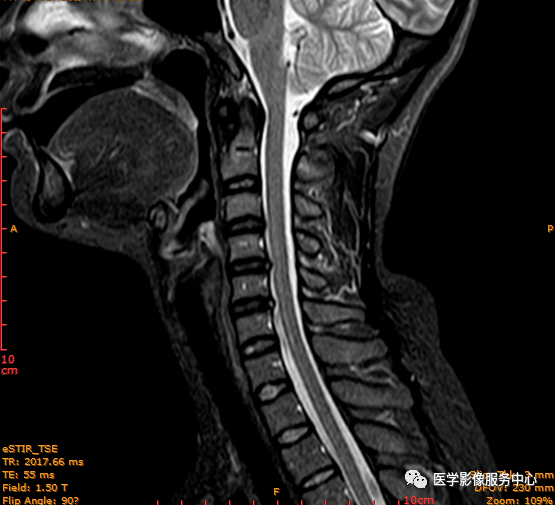

此病例为C4-5椎间盘后缘HIZ,工作中颈椎椎间盘HIZ发生率不高

图为C4-5、C5-6椎间盘后缘HIZ;